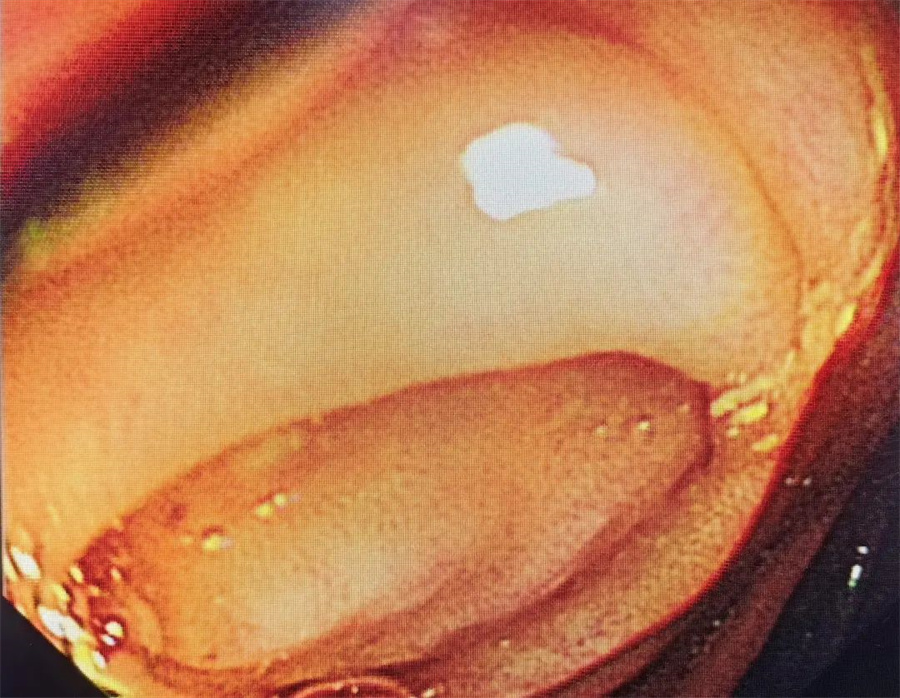

逆行性阑尾炎治疗术

边鹏主任介绍说,内镜下逆行阑尾炎治疗术,是一种新型治疗急性阑尾炎的微创方法,近年在国内逐步开展,并成功应用于临床。

与传统或外科腔镜治疗术相比,逆行性阑尾炎治疗术能够治疗单纯性阑尾炎和粪石性阑尾炎,适合任何年龄段的孩子。

整个治疗过程不用开刀,没有任何损伤,能够将阑尾作为正常的免疫器官保留下来。